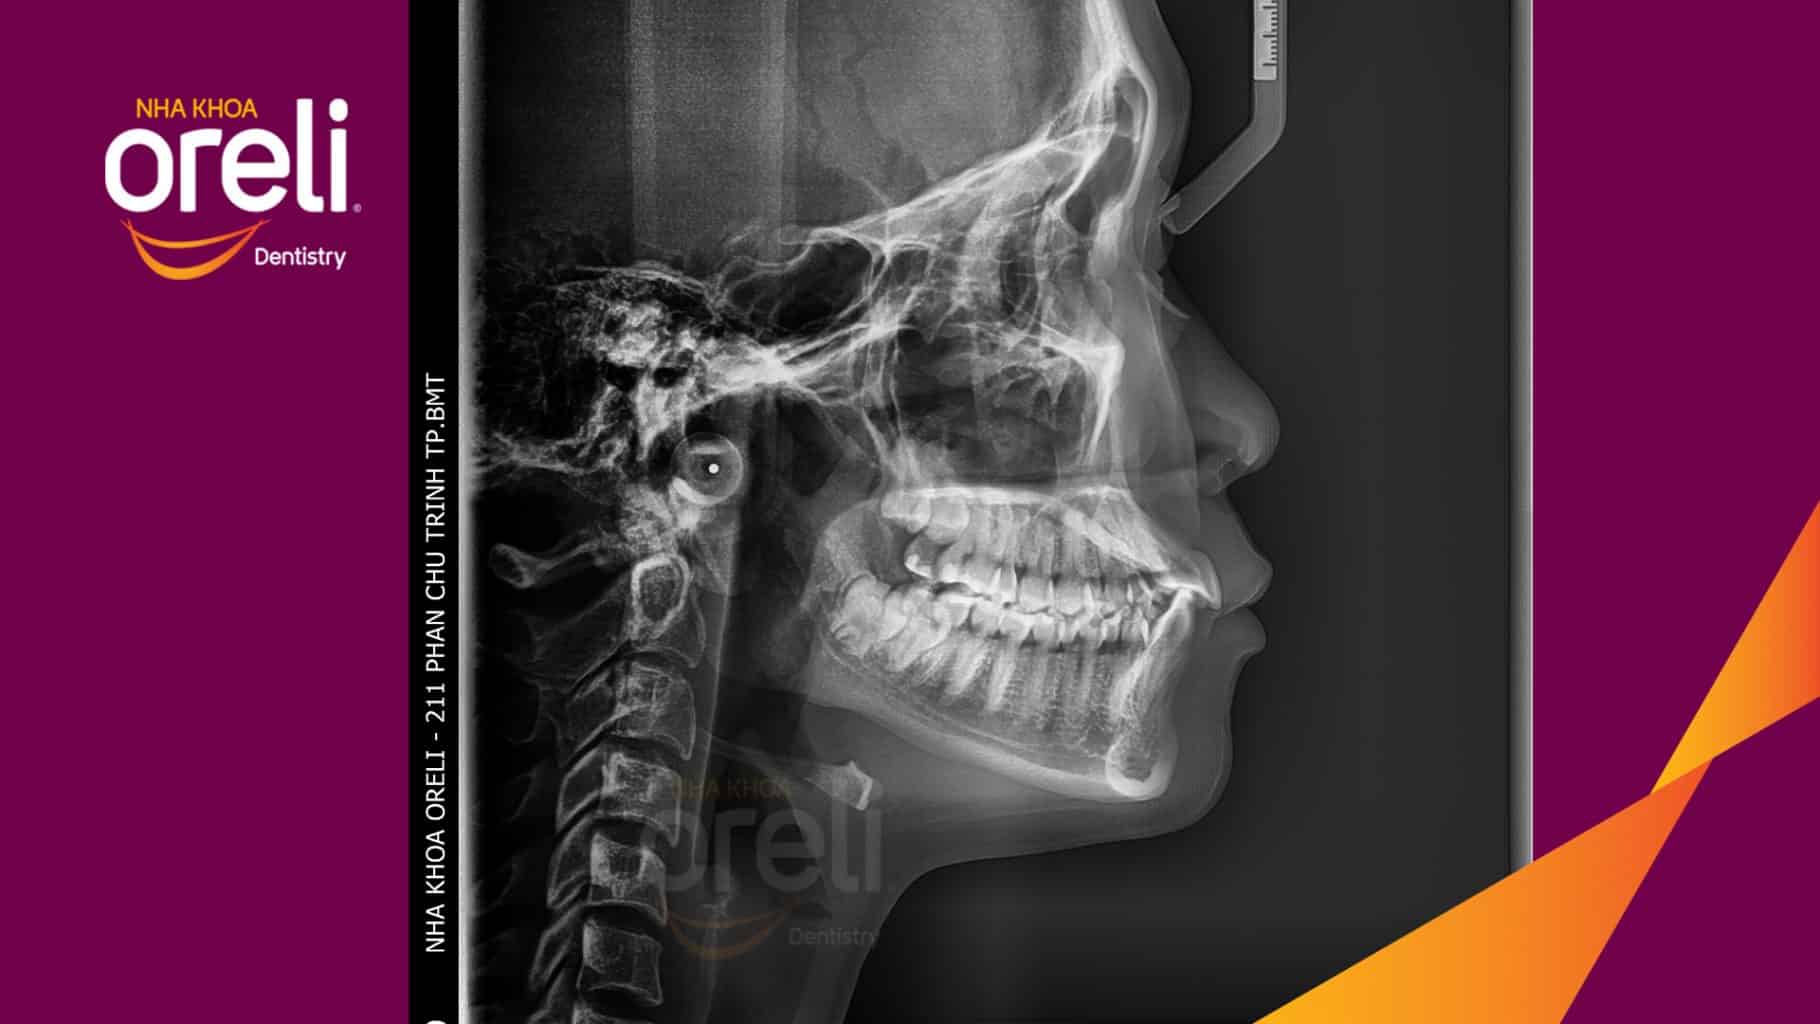

Tình trạng: Răng hô nhô xương ổ hai hàm

Giải pháp: Nhổ 4 răng số 4 niềng răng với măc cài kim loại

Trong trường hợp này độ nhô môi lớn, góc mũi môi nhọn, môi trên và dưới trượt ra trước so với đường thẩm mỹ E của Rickket, trục răng cửa hàm trên ngả trước nhiều. Việc nhổ răng 4 để giảm hô được thực hiện.